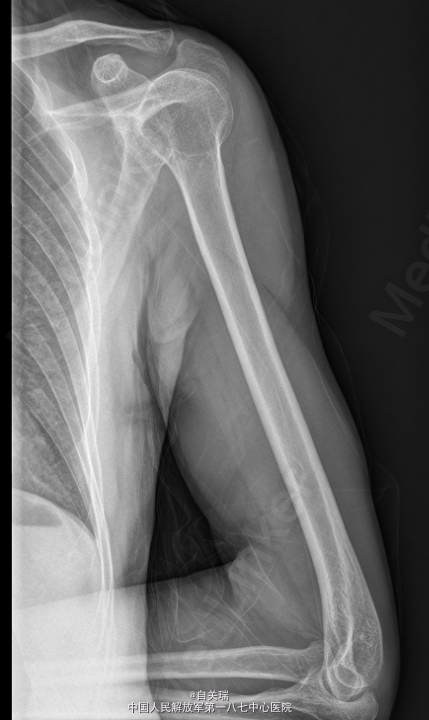

患者,男,63岁,因“发现左上臂肿块10余年左手内侧麻木1年”入院。 患者10多年前无意间发现左上臂近端内侧有一肿块,无明显压痛,无红肿,未给予重视。近1年左右肿块有所增大,触摸可出现左手内侧麻木,肢端血供正常,无明显肌肉萎缩。

左上臂近端内侧可及约4CM*5CM的肿块,质韧,周围皮肤无红肿,触摸可出现左手内侧麻木,未见有肌肉萎缩,肢端血供感觉良好。MRI: 左上臂上段内侧皮下良性占位,神经鞘瘤可能.